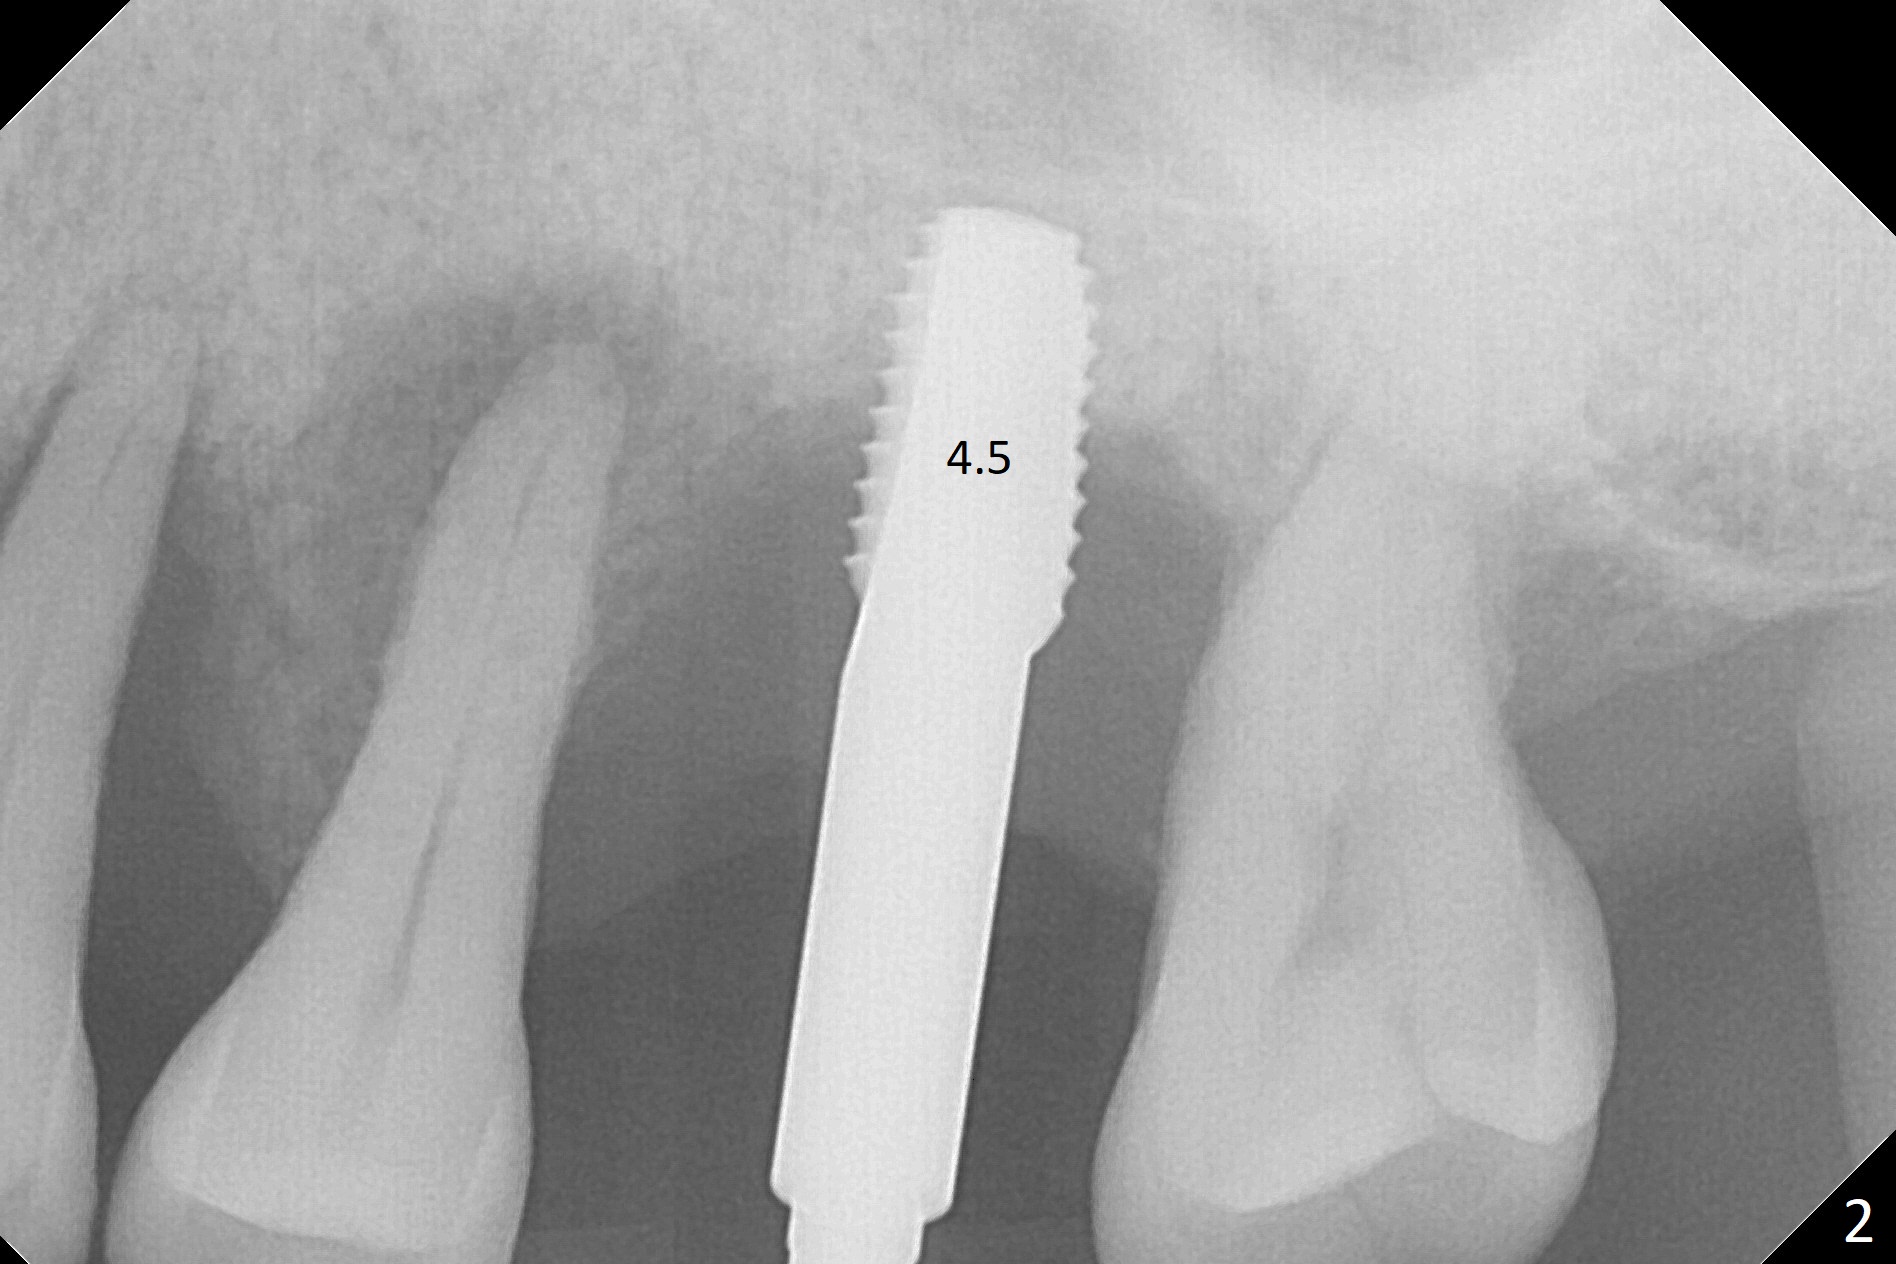

Bone height at #14 two months post exfoliation is ~ 4 mm (Fig.1). Bone expansion is difficult because of dense bone. After drilling, a 4.5 mm tap is inserted with stability (Fig.2). Sinus lift is accomplished with RT3 and autogenous bone prior to placement of a 4.5x8.5 mm implant (Fig.3). Because of flapless surgery and tight and long gingiva, bone graft around the coronal end of the implant is intentionally not placed. A 5.5x5(4) mm abutment is immediately placed for an immediate provisional. (Fig.4). Take PA and impression when the patient returns. The provisional dislodges 3.5 months postop (Fig.4); impression is taken. The patient reports hot sensitivity and pain after meal at the implant site (Fig.5). After removal of the implant crown/abutment, she feels better. If not, it seems necessary to extract the tooth #13 for a 13 mm long implant with a mill abutment (Fig.6).